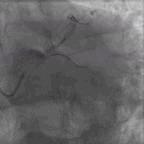

根据《中国经皮冠状动脉介入治疗指南(2016)》推荐,该患者适合CABG而非PCI。但是,患者及其家属拒绝行CABG,要求行PCI。在这种情况下,我们开始思索对该患者行PCI到底应处理哪支血管?左冠状动脉,还是右冠状动脉?经讨论后,首先对右冠状动脉进行干预(图3),治疗过程中AL.75指引导管导致右冠状动脉窦底夹层,此时很难抉择是放弃手术还是观察后干预前降支。观察10分钟后,见右冠状动脉窦底造影剂滞留逐渐消散。

图3. 对右冠状动脉行PCI